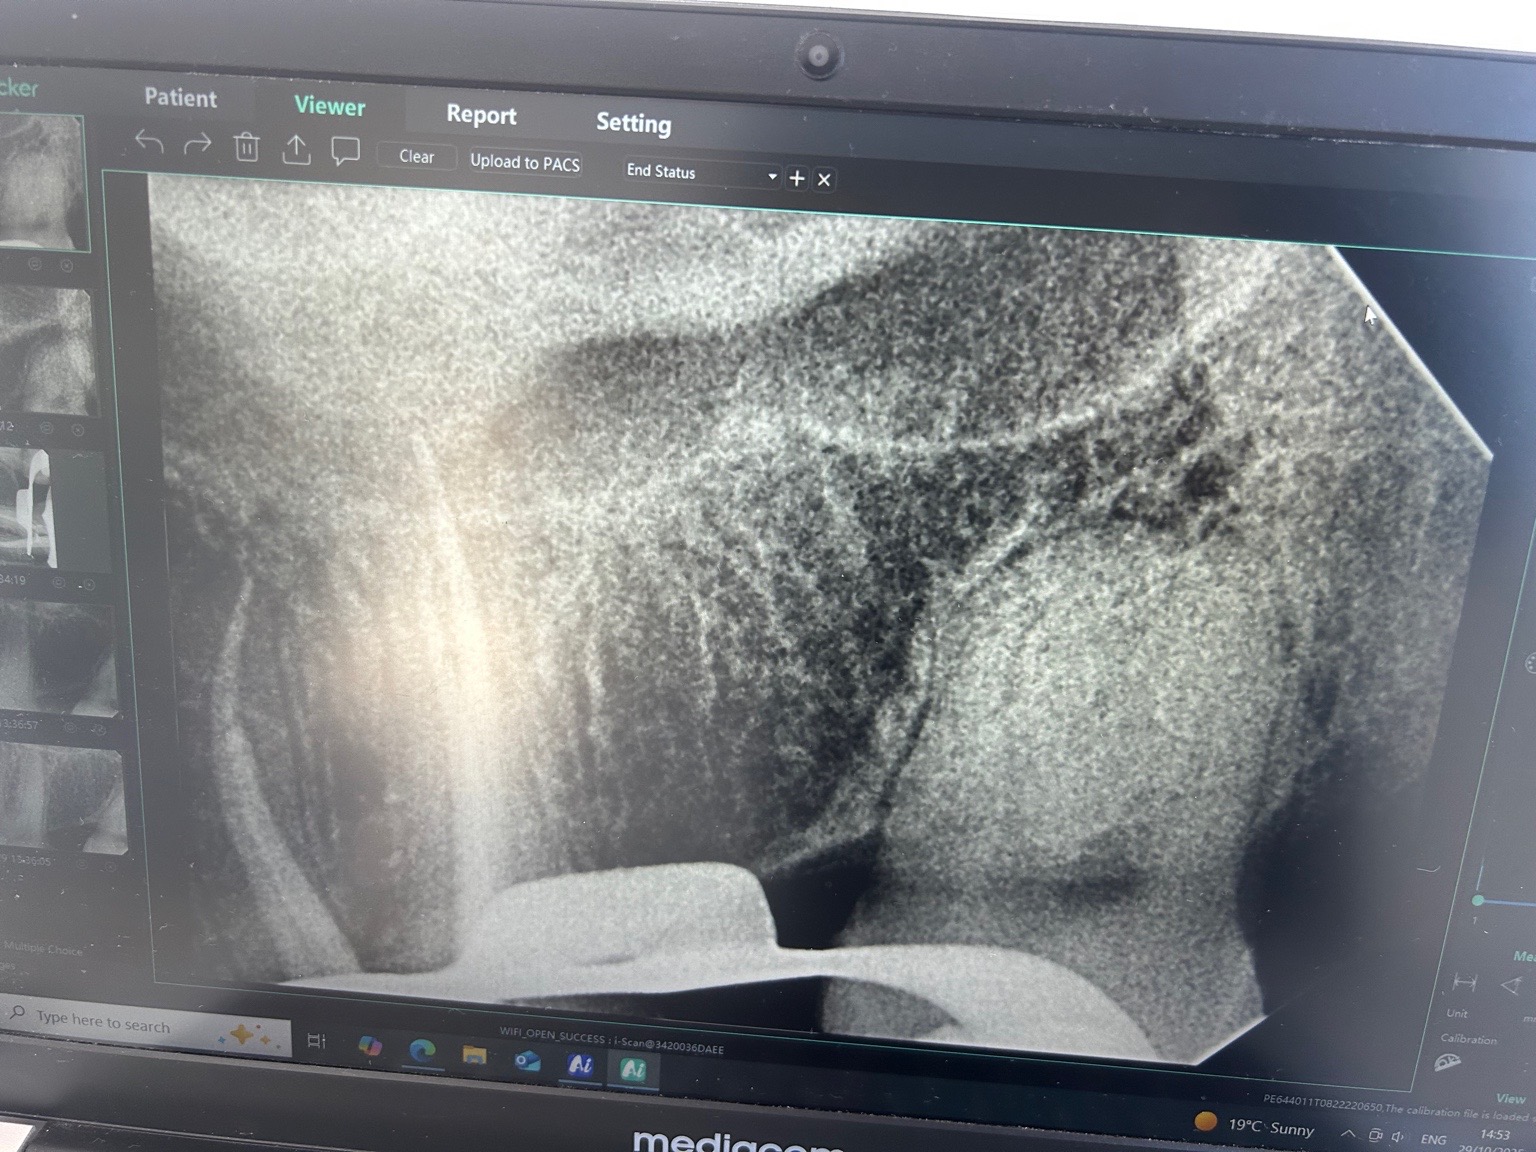

Uiteindelijk was ik in het buitenland en kreeg ik weer last. Uiteindelijk cbtc scans gedaan en microscopisch 4 kanalen. Was heftig lang. Geen verticale fracturen gevonden maar wel gevuld met glasvezel stiften. Dame werkte bij alldent in Frankfurt. Kroon vond ze met huidige stand niet nodig maar goed. Even je objectieve mening wat vindt je er van?. Ze was extreem secuur. Napijn wel met bijten maar was vanwege grote behandeling gebruikelijk. Kan nog even zeuren. Laesie was minimaal volgens haar.

Ja die indruk kreeg ik ook. Nu inderdaad afwachten. Was is hier nu meestal het proces wanneer je zegt afwachten. Ontsteking moet minder worden etc? Op de foto vond ze die minimaal maar de pulpa was al langer afgestorven. Dat afwachten is het heel proces?